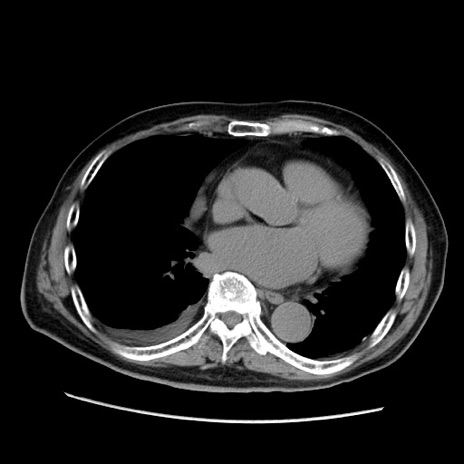

症例21(横断像)

【症例】70歳代男性

【主訴】腹痛

【現病歴】肝硬変・肝細胞癌にてかかりつけの方。約9時間前に食後より腹痛出現。症状が徐々に増悪し、嘔吐出現したため来院。

【既往歴】肝硬変、肝細胞癌(RFA、TACE後)

【身体所見】意識清明、表情苦悶様、BT 36℃、BP 129/78mmHg、P 88bpm、SpO2 97%(RA)、右上腹部から心窩部にかけて圧痛あり、反跳痛なし、筋性防御あり。

【データ】WBC 5800、CRP 0.16